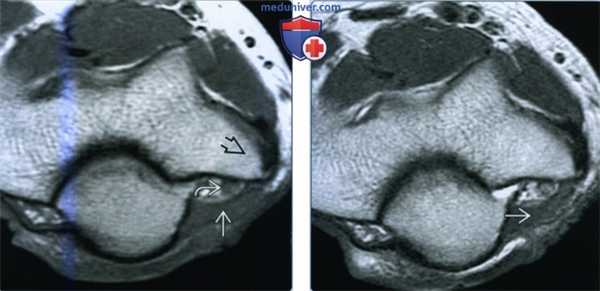

(Слева) На осевой MPT Т1ВИ у этого же пациента визуализируется надблоково-локтевая мышца, образующая верхнюю стенку локтевого канала кзади от медиального мыщелка плечевой кости Локтевой нерв находится в локтевом канале и может быть сдавлен, что приводит к нейропатии локтевого нерва.

(Справа) Осевая MPT Т2 ВИ у этого же пациента на этом же уровне подтверждает, что надблоково-локтевая мышца соответствует сигналу от нормальной мышцы на всех частотах, что свидетельствует об идентичности.